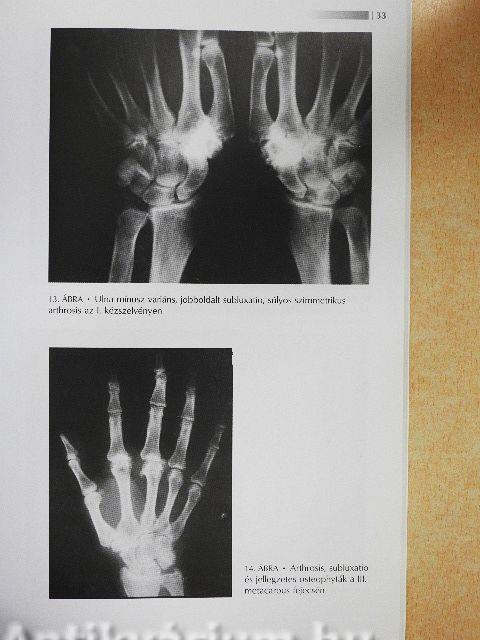

Az arthrosis31